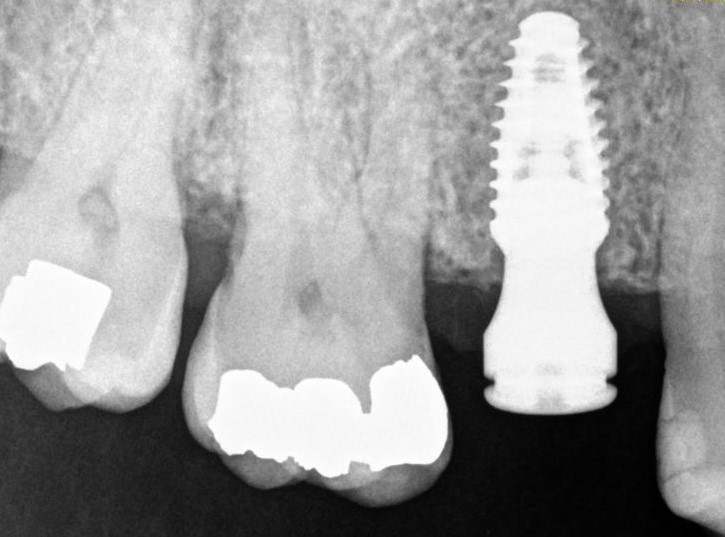

Are you interested in a dental implants to replace a missing tooth, stabilize a denture, or replace multiple missing teeth? Check out our office! Dr. Branson has completed extensive dental implant training. He utilizes a digital approach to pre-plan your surgery, to minimize time in the dental chair, and achieve the best long term result!